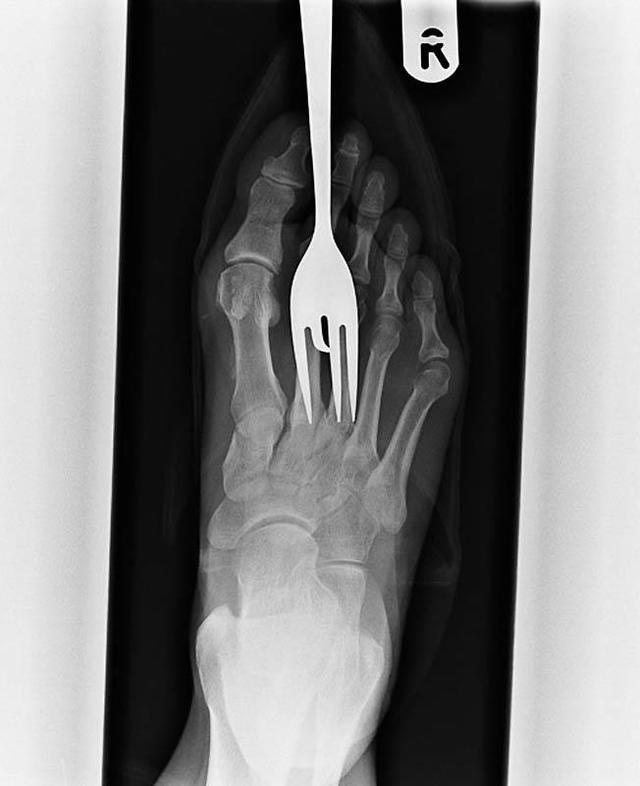

Рентген пациента, который наступил на вилку.